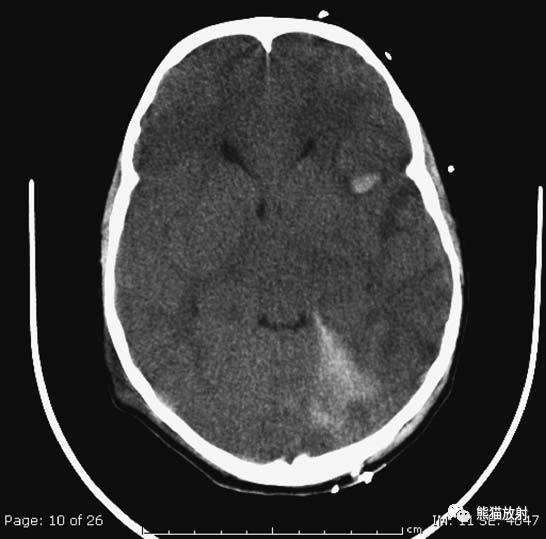

5、高血压性脑出血

高血压性脑出血:

- 自发性出血;

- 继发于长期高血压及慢性血管病;

- 常见于基底节区、丘脑、脑桥、小脑。

A:占位效应,相邻脑沟、脑池消失;F:脑出血破入四脑室。

基底节区大量高血压性脑出血,破入脑室及蛛网膜下腔,周围水肿,脑干周围空间消失;脑干出血、脑积水。